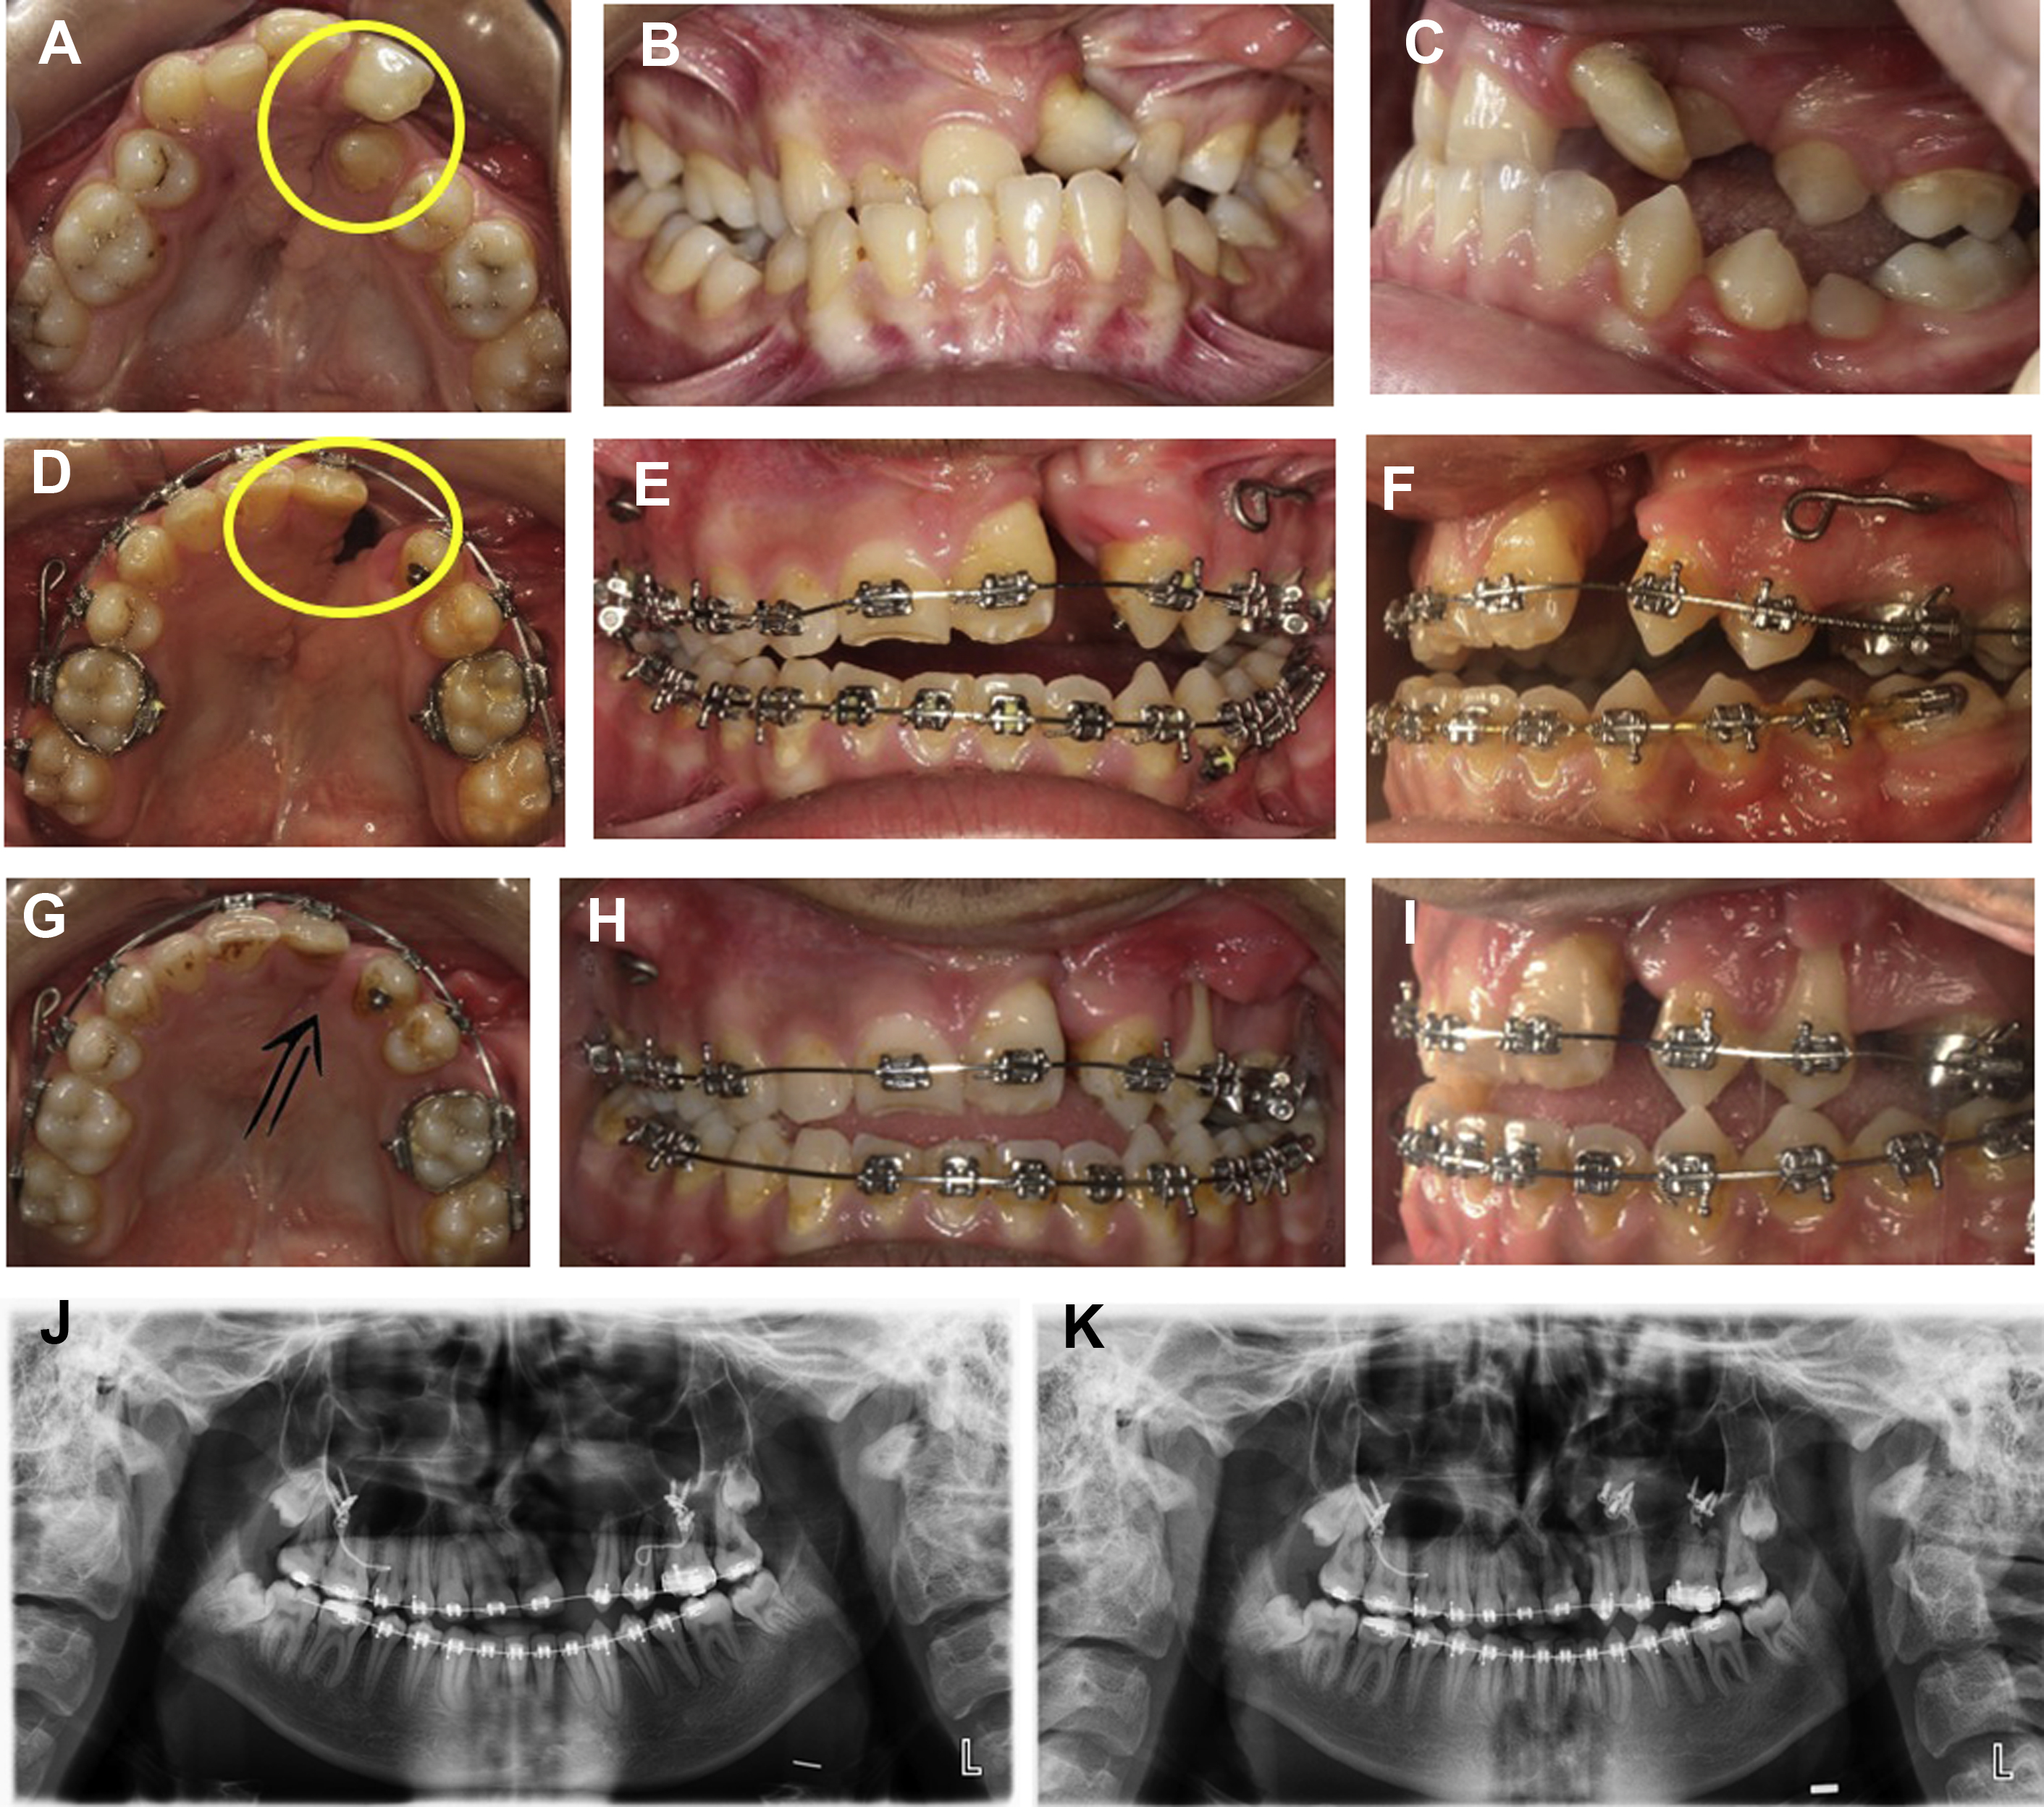

An 18-year-old man with unilateral cleft lip and palate presents with a large oronasal fistula and an alveolar cleft on the left side ( Fig. 1 A–C). Alveolar distraction was planned to reduce the alveolar cleft following presurgical orthodontics. After inserting brackets and arch wires, maxillary teeth were aligned and an extremely rotated left incisor tooth was derotated. The lesser segment was expanded by using arch wires ( Fig. 1 D–F). After 11 months of fixed orthodontic treatment, a fabricated alveolar distractor was applied to the lesser segment. The activation rate was 0.5 mm/d with twice-daily activation for a period of 3 weeks. The same distractor was used during the consolidation period of 4.5 months ( Fig. 1 G, H). Alveolar bone graft was performed after consolidation was completed. A gingival recession occurred at the maxillary first premolar ( Fig. 1 I). Postoperative panoramic radiograph showed narrowing of the alveolar cleft and new bone at the cleft site compared with the presurgical panoramic radiograph ( Fig. 1 J, K). Orthognathic surgery was planned for the maxillomandibular discrepancy.